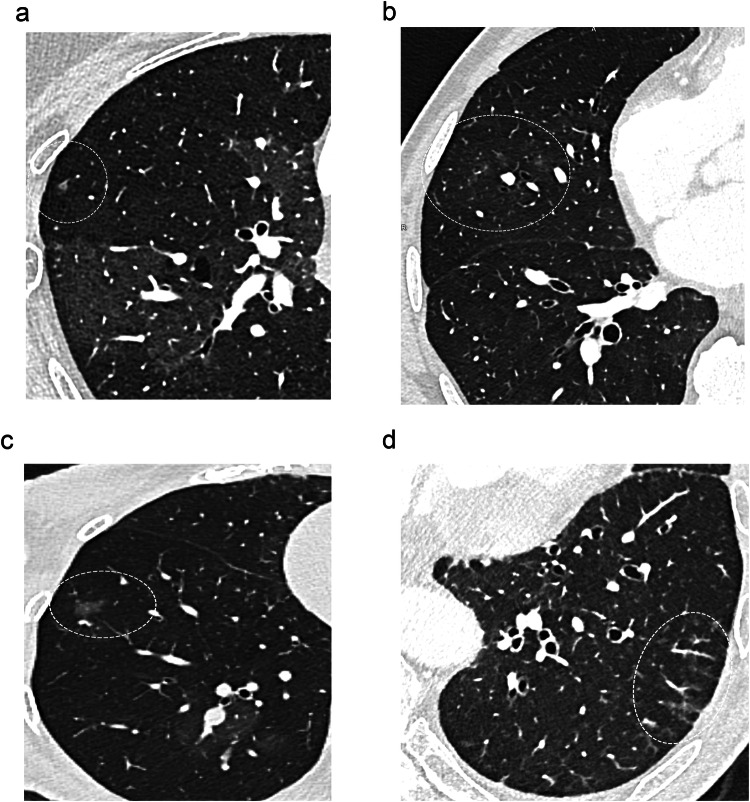

目的:探讨慢性血栓栓塞性肺动脉高压(CTEPH)患者肺微血管病变的CT表现。材料与方法:对29例患者进行高空间分辨率光子计数检测器(PCD)-CT扫描。每位患者最多选择三对,每对由马赛克灌注的高衰减区和低衰减区组成。结果:86对病例的对比分析表明:(a)低衰减区微结节不清晰(p = 0.008)、小叶磨玻璃混浊(p = 0.01)和模糊(p = 0.003)的发生率较高;(b)新生血管频率无显著差异(p = 0.43)。在22例中枢性和外周性CTEPH患者的66对研究中,在低衰减区观察到类似的趋势;在7例外周性CTEPH患者的20对患者中,发现微结节不清晰、小叶磨玻璃样混浊、高衰减区模糊。平均肺动脉压≤42 mmHg(即平均肺动脉压中位数)的患者有45对,显示微结节定义不清(p = 0.003)和模糊(p 42 mmHg)的频率更高。结论:提示微血管病变的CT表现多出现在低灌注区,严重ph患者的CT表现有均匀化的趋势。关键点:肺微血管病变在血栓动脉内膜切除术成功后残余肺动脉高压的起源中起着至关重要的作用,目前超出了影像学的范围。发现CTEPH在远端肺循环水平的形态学异常在马赛克灌注的各个区都有表现。本研究提示,PCD-CT的高空间分辨率具有接近CTEPH小血管病变复杂病理生理的能力,为治疗决策提供重要信息。

Purpose: To evaluate CT findings suggestive of lung microvasculopathy in patients with chronic thromboembolic pulmonary hypertension (CTEPH).

Materials and methods: Twenty-nine patients were scanned with high-spatial resolution on a photon-counting detector (PCD)-CT unit. A maximum of three pairs per patient, each composed of hyper- and hypo-attenuating areas of mosaic perfusion, were selected.

Results: Comparative analysis of the 86 selected pairs showed: (a) a higher frequency of ill-defined micronodules (p = 0.008), lobular ground-glass opacities (p = 0.01) and haziness (p = 0.003) in hypoattenuated areas; (b) there was no significant difference in the frequency of neovascularity (p = 0.43). Similar trends were observed in hypoattenuating areas of the 66 pairs studied in the 22 patients with central and peripheral CTEPH; an absence of ill-defined micronodules, lobular ground-glass opacities, and haziness in hyperattenuating areas was noticed in the 20 pairs studied in the 7 patients with peripheral CTEPH. Patients with a mean pulmonary artery pressure ≤ 42 mmHg (i.e., the median value of mean pulmonary artery pressure) had 45 pairs compared, showing a higher frequency of ill-defined micronodules (p = 0.003) and haziness (p < 0.001) in hypoattenuated areas, together with a higher frequency of subpleural systemic-to-pulmonary anastomoses (p = 0.02). There were no statistical differences in the frequency of CT findings between hypo- and hyper-attenuating areas in the 41 pairs of patients with a mean pulmonary artery pressure > 42 mm Hg.

Conclusion: CT features suggestive of microvasculopathy were more frequent in areas of hypoperfusion, with a trend toward homogenization of CT findings in patients with severe PH.

Key points: Question Lung microvascular lesions play a crucial role in the origin of residual pulmonary hypertension after successful thromboendarterectomy, currently beyond the scope of imaging. Findings The expected morphological abnormalities at the level of distal pulmonary circulation in CTEPH were found to be depictable in each zone of mosaic perfusion. Clinical relevance This study suggests that the high-spatial resolution of PCD-CT has the capability of approaching the complex pathophysiology of small-vessel disease in CTEPH, providing important information prior to therapeutic decisions.